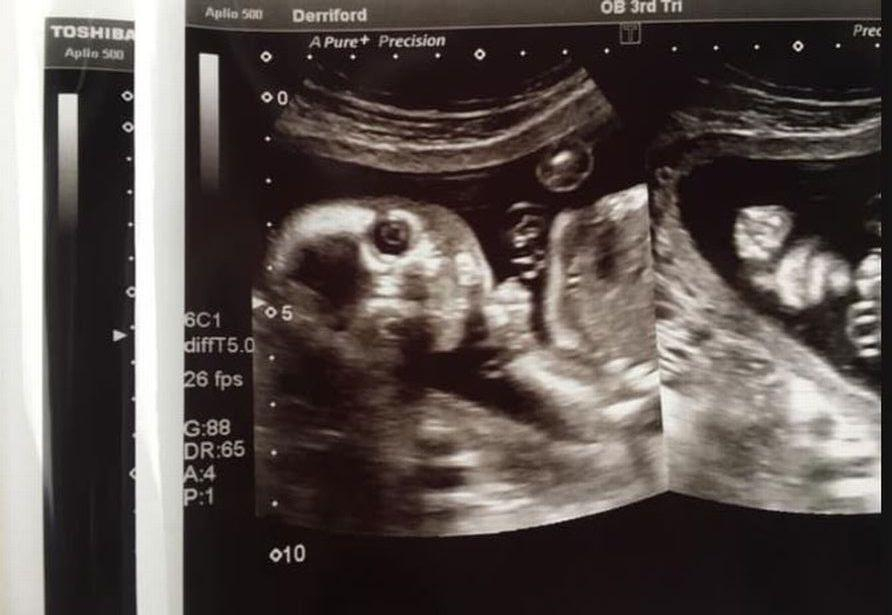

Дело в том, что во время сканирования малыш повернулся в утробе и посмотрел прямо в УЗИ-аппарат. Джо Грир и её врач в больнице Деррифорда, Англия, не могли перестать смеяться, хоть выглядело это немного жутко.

"Вы все видели эти обычные снимки с ультразвукового сканирования, но так выглядит наш. Конечно, есть и нормальные кадры, но этот особенно смешной и редкий", - подписала снимок Джо Грир.